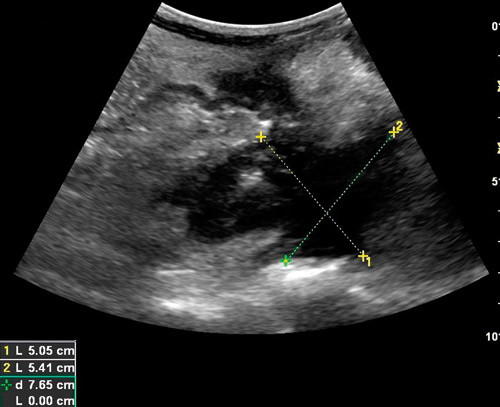

Stenoser kan forekomme ved Crohns sykdom (fig 3). Man ser da ofte betydelig fortykket vegg og avsmalnet lumen og en prestenotisk utvidelse. Den fortykkede tarmveggen i stenosen har liten eller ingen motilitet. Bortfall av lagdeling i stenosen indikerer ødem i tarmveggen og sannsynlig akutt inflammasjon, mens mer bevart lagdeling kan indikere fibrose (18). Det er viktig for valg av behandling å vite om den fortykkede veggen i en stenose skyldes hovedsakelig aktiv inflammasjon eller fibrose. Ved aktiv inflammasjon kan pasienten ha nytte av medisinsk behandling, mens kirurgi vanligvis er indisert ved kroniske betennelsesforandringer og fibrose (18). Hvis man ved hjelp av fargedoppler ser rikelig med kar i stenoseområdet, tolkes det som et uttrykk for inflammatorisk aktivitet. Da kan medikamentell behandling være verdt å forsøke. Ultralyd er i flere studier brukt til å påvise stenoser hos pasienter med Crohns sykdom. I disse studiene har ultralyd en sensitivitet på 74 – 100 % og en spesifisitet på 91 – 100 % (9, 14, 19).